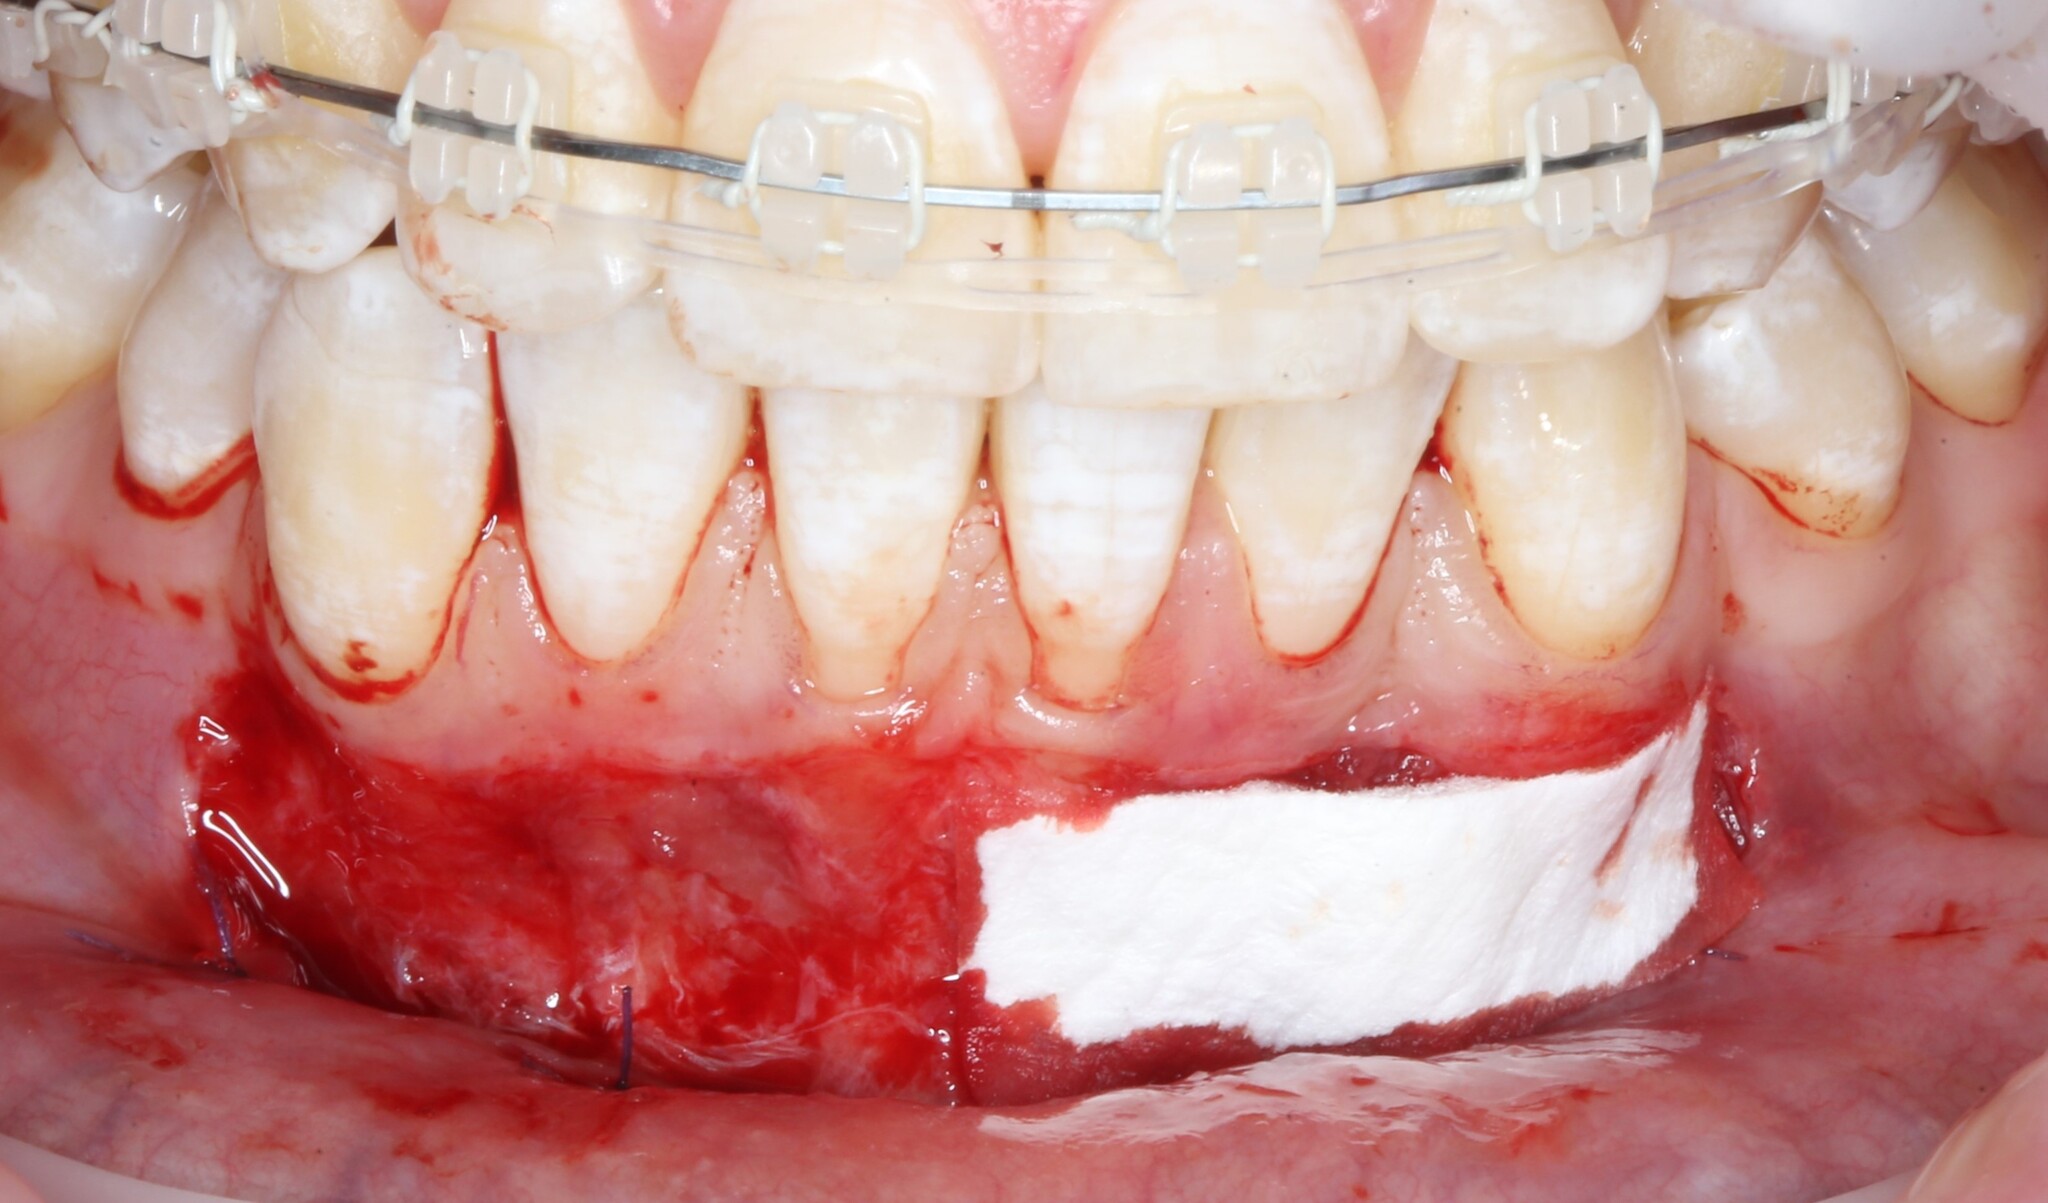

Для того, чтобы операция была менее травматична и не пришлось брать свою собственную слизистую, вырезав кусок с неба, используется коллагеновая мембрана. Выглядит она так:

Приложили:

Теперь подшиваем c одной стороны: